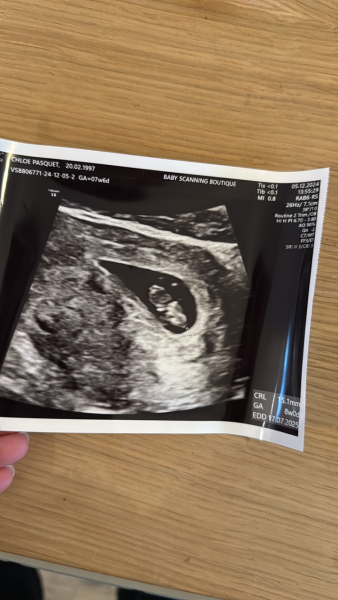

This was mine at 7+6 (measuring 8+0) so I'm hopeful you'll get a nice clear scan ❤️

Let us know after but I 100% know how crippling the anxiety is. My 4 year old has just been poorly and it's been mentally exhausting for me, the anxiety is awful!